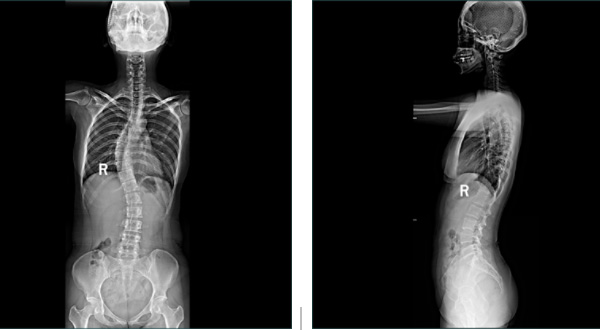

玉中影像檢查再升級(jí)—— 全脊柱及雙下肢全長拼接攝影系統(tǒng)投入使用

近日,玉溪市中醫(yī)醫(yī)院放射科島津C200第五代動(dòng)態(tài)大平板透視攝影系統(tǒng)投入使用,該設(shè)備可開展全脊柱、雙下肢全長檢查。高清攝影、快速診斷、及時(shí)治療,實(shí)現(xiàn)了全脊柱、雙下肢全長檢查的“無縫拼接”,是脊柱側(cè)彎和下肢畸形等骨科疾病術(shù)前術(shù)后X線檢查的首選方法。

放射科主任吉德磊介紹:“以前拍片子需要好長時(shí)間,需多次擺位。由于平板探測(cè)器最大規(guī)格一般只有43cm左右,而脊柱和下肢全長一般超過了這個(gè)長度,現(xiàn)采用新系統(tǒng)實(shí)現(xiàn)全脊柱及雙下肢全長X線攝片,能直觀的顯示全脊柱、雙下肢全長的整體形態(tài),在一張照片上可獲得較清晰、完整的全景圖像顯示,并可進(jìn)行相關(guān)長度測(cè)量、角度測(cè)量等應(yīng)用。”

成功解決了在觀察頸椎至尾椎的脊柱側(cè)彎或其他病變時(shí)不能一次成像的問題。

便捷:一次成像,無縫拼接!

常規(guī)DR不能一次性完成全脊柱或全下肢X光影像拍攝,需分別拍攝頸椎、胸椎、腰椎、骶尾椎的X光片,只能觀察到局部的側(cè)彎情況,看不到三者之間的連續(xù)性,增加了這類疾病的診治難度。

市中醫(yī)醫(yī)院放射科這臺(tái)高端懸吊DR具有千萬級(jí)像素,利用其特有的“無縫拼接”技術(shù),可獲得一幅完整的全脊柱和全下肢影像,為臨床在脊柱側(cè)彎畸形和下肢骨關(guān)節(jié)病變?cè)\斷、治療方案制定及術(shù)后復(fù)查提供精準(zhǔn)的測(cè)量。

2、對(duì)于脊柱側(cè)彎的診斷治療、手術(shù)方案的制定等都有著極其重要的參考價(jià)值。